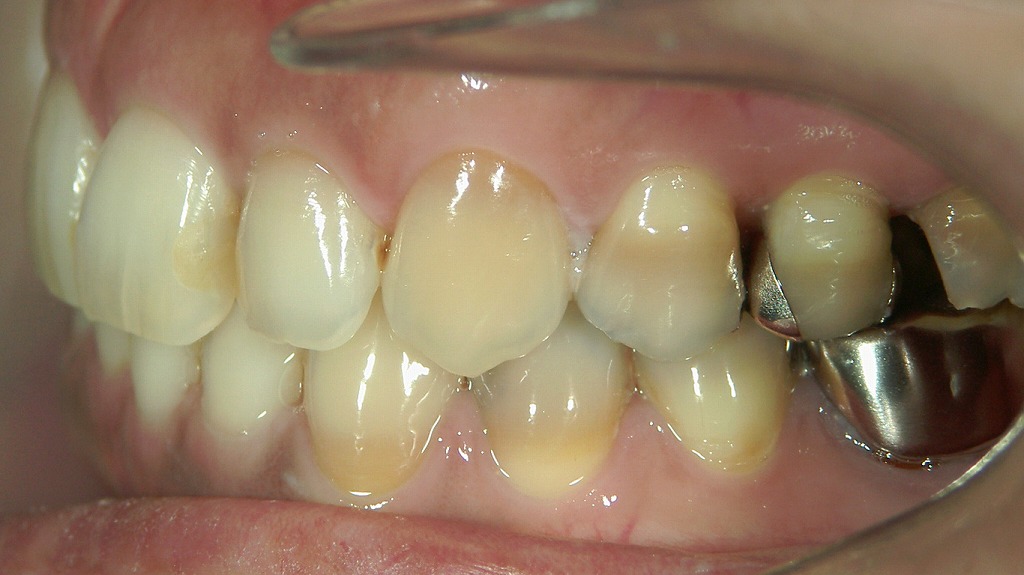

- 3.1.2.1. 1枚目:ホワイトニング前の歯の状態

1枚目:ホワイトニング前の歯の状態

最初の写真では、歯全体がやや黄ばみを帯びています。

特に前歯の色味が自然な範囲にあるものの、ややA2〜A3相当の黄みが確認できます。

これは日本人に多い「生活習慣による着色(ステイン)」や「加齢による象牙質の色」が透けて見えている状態です。

- 歯の表面に大きな汚れはなく、清潔に管理されている

- ただし自然歯特有の黄ばみが均一に見られる